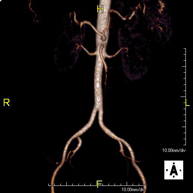

Prueba diagnóstica no invasiva que consiste en la obtención de imágenes de alta definición anatómica de todo el cuerpo mediante el empleo de un campo electromagnético y ondas de radio (con un emisor y un receptor). No utiliza radiación ionizante. Es una prueba muy importante en la búsqueda de metástasis en pacientes con neoplasia conocida. No requiere preparación previa. No es necesario el empleo de contraste paramagnético (Gadolinio). - Angio-RM Aorta abdominal

Prueba diagnóstica no invasiva que consiste en el estudio de la arteria aorta abdominal, obteniendo imágenes de alta definición anatómica mediante el empleo de un campo electromagnético y ondas de radio (con un emisor y un receptor). Es indispensable el uso de contraste paramagnético (Gadolinio). Sin embargo, no utiliza radiación ionizante. La calidad de las imágenes permite realizar reconstrucciones en 2D y 3D. Está indicado en aquellos pacientes con enfermedad vascular (aterosclerosis), estudio de aneurismas, en estudios pre-quirúrgicos de lesiones adyacentes a la aorta abdominal como "mapa" vascular, etc. - Angio RM Aorta-ilíaca

Prueba diagnóstica no invasiva que consiste en el estudio de la arteria aorta abdominal de las arterias ilíacas, obteniendo imágenes de alta definición anatómica mediante el empleo de un campo electromagnético y ondas de radio (con un emisor y un receptor). Es indispensable el uso de contraste paramagnético (Gadolinio). Sin embargo, no utiliza radiación ionizante. La calidad de las imágenes permite realizar reconstrucciones en 2D y 3D. Esta prueba está especialmente indicada como estudio pre-quirúrgico (mapa vascular) antes de intervenciones percutáneas o quirúrgicas de aorta abdominal y arterias ilíacas, estudio complementario en pacientes con isquemia de miembros inferiores, etc. - Angio RM Arterial extremidades inferiores